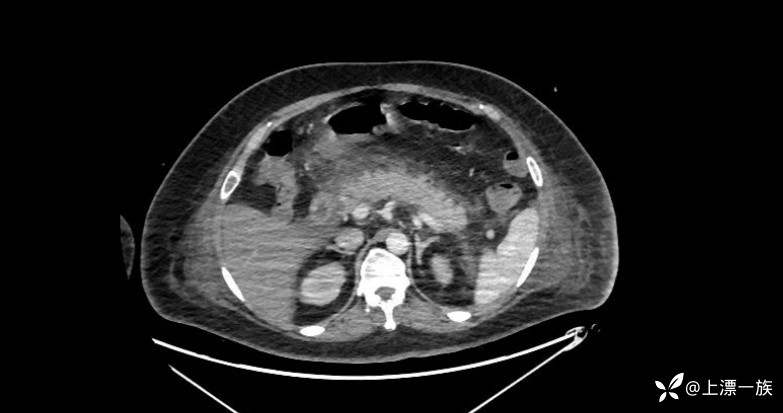

复查CT腹部